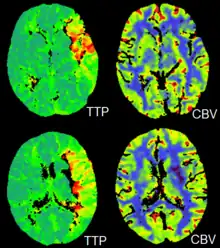

CT perfusion imaging

CT perfusion imaging is a specific form of CT to assess flow through blood vessels whilst injecting a contrast agent.[21] Blood flow, blood transit time, and organ blood volume, can all be calculated with reasonable sensitivity and specificity.[21] This type of CT may be used on the heart, although sensitivity and specificity for detecting abnormalities are still lower than for other forms of CT.[22] This may also be used on the brain, where CT perfusion imaging can often detect poor brain perfusion well before it is detected using a conventional spiral CT scan.[21][23] This is better for stroke diagnosis than other CT types.[23]